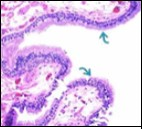

Alternatively, cutaneous ciliated cyst can be lined by non ciliated cuboidal or columnar epithelium with intermingled intercalated, dark or round peg cells. Foci of squamous metaplasia can be occasionally exemplified in the adherent epithelium whereas mucinous cells or apocrine-like features are exceptional 6, 8. Figure 1, Figure 2, Figure 3, Figure 4, Figure 5, Figure 6, Figure 7, Figure 8, Figure 9, Figure 10, Figure 11, Figure 12. 11, 12, 13, 14, 15, 16, 17, 18, 19.

Figure 2.Ciliated cutaneous cyst with an undulating layer of ciliated cuboidal epithelium and supporting fibrous tissue framework (12).